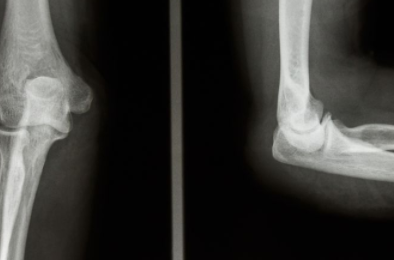

3、关节镜的应用

在膝盖的半月板损伤以后利用关节镜进行检查,因为半月板边缘如果有撕裂情况的话,可以利用缝合这种方法来修复,通常进行半月板部分切除,没有受损的部位进行保留。起到一个很好的治疗效果,除此以外也可以利用关节镜手术进行治疗,效果也是比较好的。